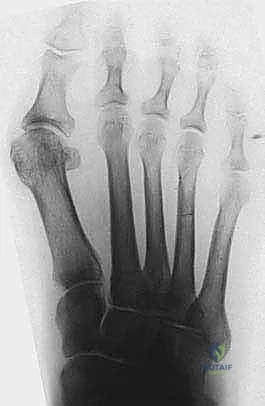

- الأشعة السينية (X-Rays) أثناء تحمل الوزن: هذا هو الفحص الذهبي. يجب أن تُؤخذ صور الأشعة والمريض واقف (يتحمل وزنه على قدميه). من خلال هذه الأشعة، يقوم الدكتور هطيف بقياس الزوايا الهامة بدقة هندسية:

- تقييم موضع العظام السمسمية: لمعرفة مدى خروجها عن مسارها.

- تقييم حالة المفصل: للبحث عن أي علامات لخشونة المفاصل (Arthritis) التي قد تغير من خطة العلاج.